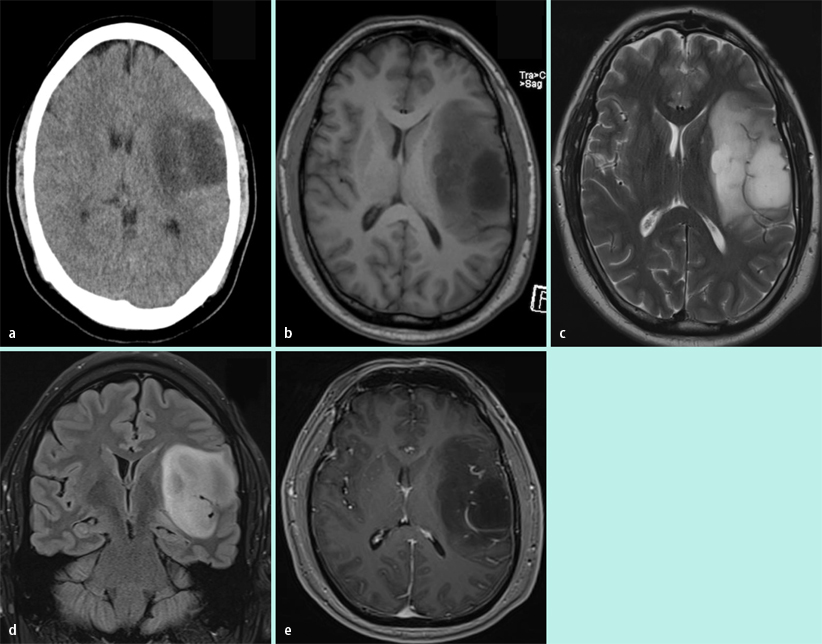

Astrocytoma (NOS)Grade 2 Image. Erfahrungen, die uns irgendwie weiterhelfen können sehr dankbar!!!! Gespeichert brifabi Gast; Re:Diffuses Astrozytom Grad II in dem Du bereits jetzt aus den Erfahrungen vieler Betroffener schöpfen kannst, indem Du in den entsprechenden Bereichen liest

Astrocytoma (NOS)Grade 2 Image. Bis vor einem Jahr war der Tumor nicht mehr weiter gewachsen Hallo, ich bin 24 und bei mir wurde durch Zufallsbefund ein Astrozytom Grad II gefunden